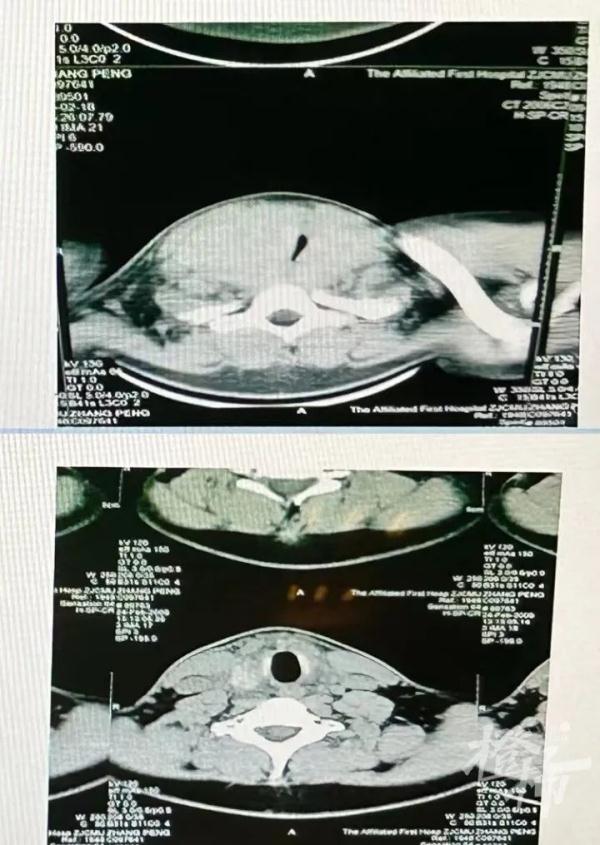

20岁的小雨也有类似的经历,他比小玲的情况更严重,他来医院时吐气都很困难,睡觉时出现了严重的打呼声,甚至影响到了在隔壁睡觉的父母。通过甲状腺B超检查,小雨的气道被甲状腺肿瘤严重压迫。“原本通畅的气道被压迫到只剩一道极窄的缝隙,所以他才会出现吐气困难、打呼严重的情况。”医生说。手术后,小雨终于恢复正常,能够顺畅吐气了。

小雨手术前后的气道对比图。(医院供图)